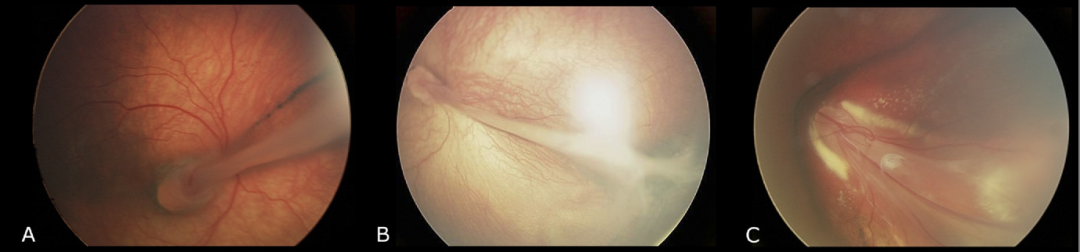

家族性渗出性玻璃体视网膜病变(FEVR)的视网膜褶皱表型[2]